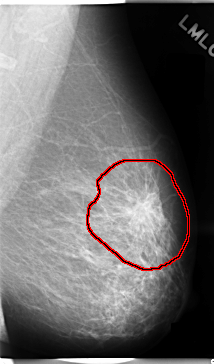

C_0089_1.LEFT_CC

LEFT_CC LINES 4672 PIXELS_PER_LINE 2784 BITS_PER_PIXEL 12 RESOLUTION 50 OVERLAY

FILE: C_0089_1.LEFT_CC.OVERLAY

TOTAL_ABNORMALITIES 1

ABNORMALITY 1

LESION_TYPE MASS SHAPE IRREGULAR MARGINS SPICULATED

ASSESSMENT 5

SUBTLETY 5

PATHOLOGY MALIGNANT

TOTAL_OUTLINES 1

BOUNDARY